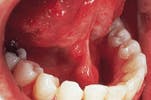

Case 8

Verrucous carcinoma

1. Identify the most important etiologic factor linked to verrucous carcinoma.

a. sun exposure

b. alcohol consumption

c. pipe smoking

d. smokeless tobacco products

e. none of the above

2. Identify the TRUE statement concerning verrucous carcinoma.

a. comprises 20% of all oral cancers

b. exhibits a warty surface texture

c. occurs on the tongue and lip

d. metastasis occurs early

e. painful when compressed

3. Identify the treatment of choice for verrucous carcinoma.

a. none

b. cryosurgery

c. surgical excision

d. chemotherapy

e. radiation therapy

4. Identify the FALSE statement concerning verrucous carcinoma.

a. occurs only in males

b. occurs in older adults

c. asymptomatic and slow growing

d. resembles a "frozen doormat"

e. usually appears white

CASE 8: 1 = d; 2 = b; 3 = c; 4 = a